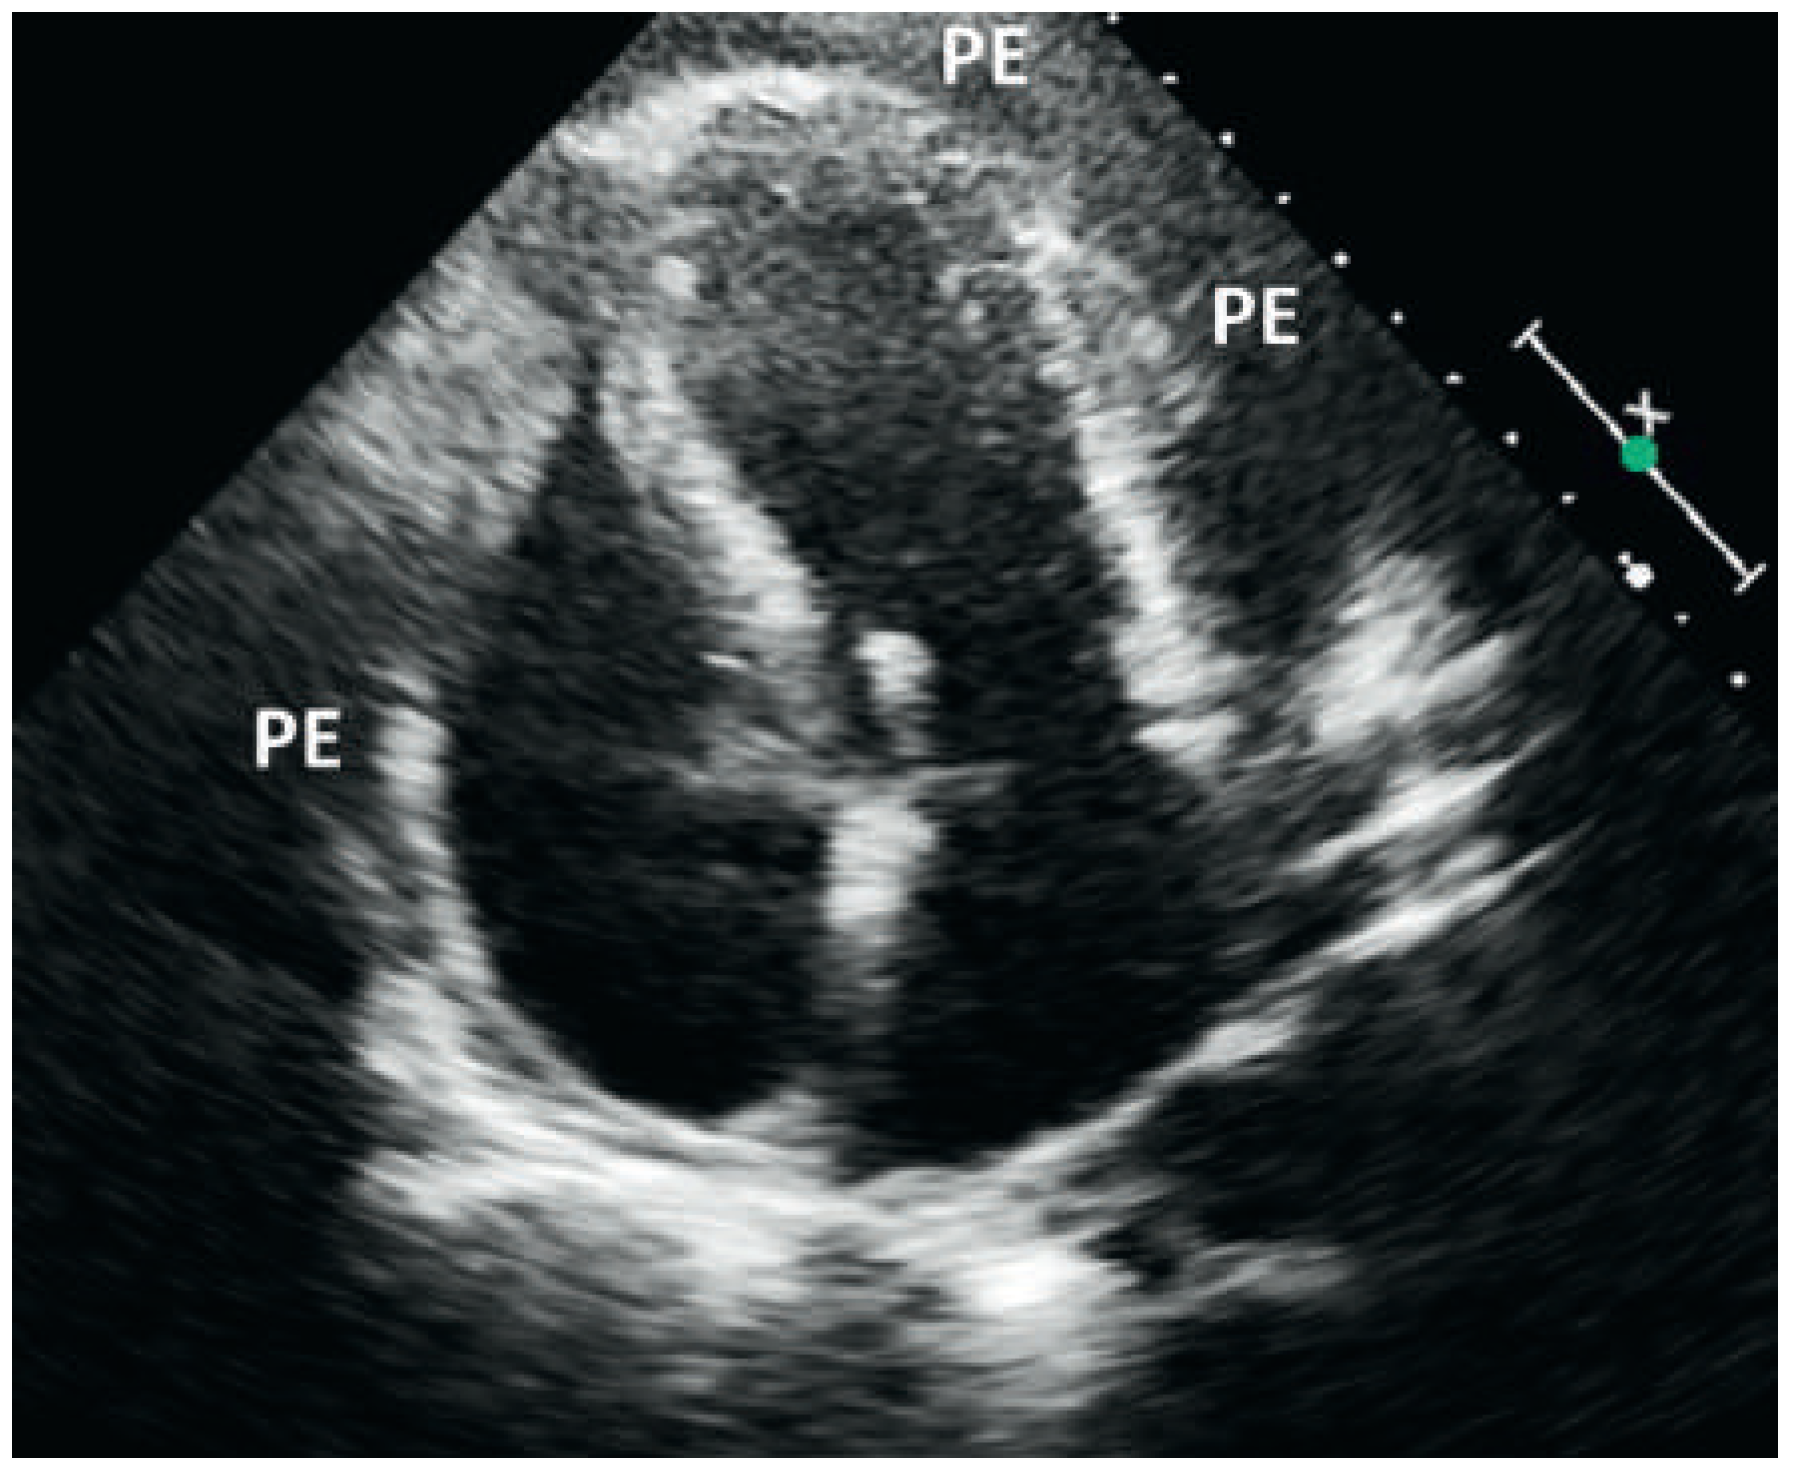

Kussmaul's Sign in Effusive Constrictive Pericarditis